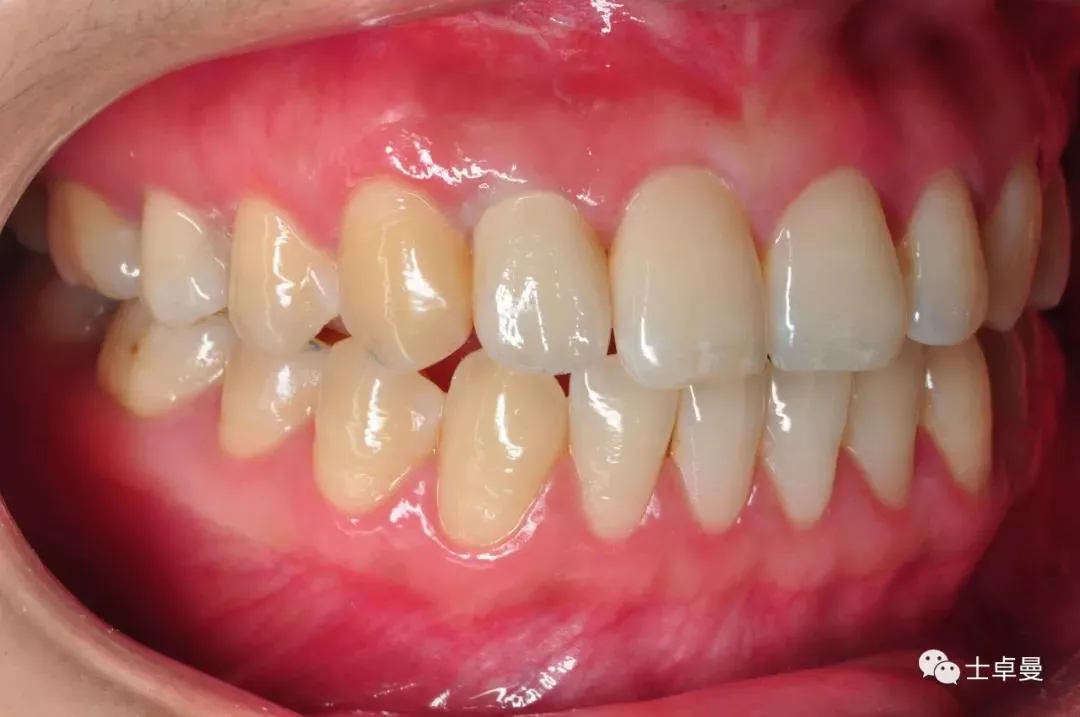

临时义齿口内就位

·        根尖片显示临时基台就位良好,无骨阻挡;

·        CBCT显示种植体三维位置良好;

·       10天后拆线,临时义齿稳定,牙龈愈合良好;